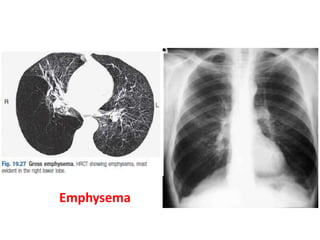

Emphysema

• Chest X-ray PA view showing

hypertransluscencs lung fields, low flat

diaphragm and widening of rib space,

suggestive of Emphysema.

Emphysema • Chest X-rayPA view showing hypertransluscencs lung fields, low flat diaphragm and widening of rib space, suggestive of Emphysema.